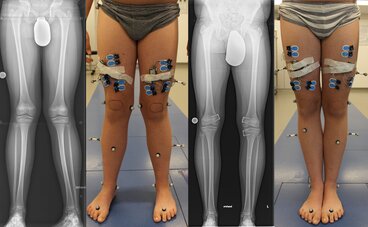

Die Forschungsschwerpunkte umfassen die Analyse und Optimierung der Ganganalyse bei orthopädischen und neurologischen Erkrankungen, insbesondere bei Kindern mit Zerebralparese, idiopathischen Knicksenkfüßen, Achsfehlstellungen der unteren Extremitäten und der Wirbelsäule.

Dabei stehen die Bewertung und Behandlung von Gangabweichungen durch chirurgische Eingriffe, Orthesen und Rehabilitationstechniken im Fokus, ergänzt durch den Einsatz von 3D-Bewegungserfassung und dynamischer Analyse zur Diagnostik und Therapieoptimierung, insbesondere unter Berücksichtigung des Wachstums.